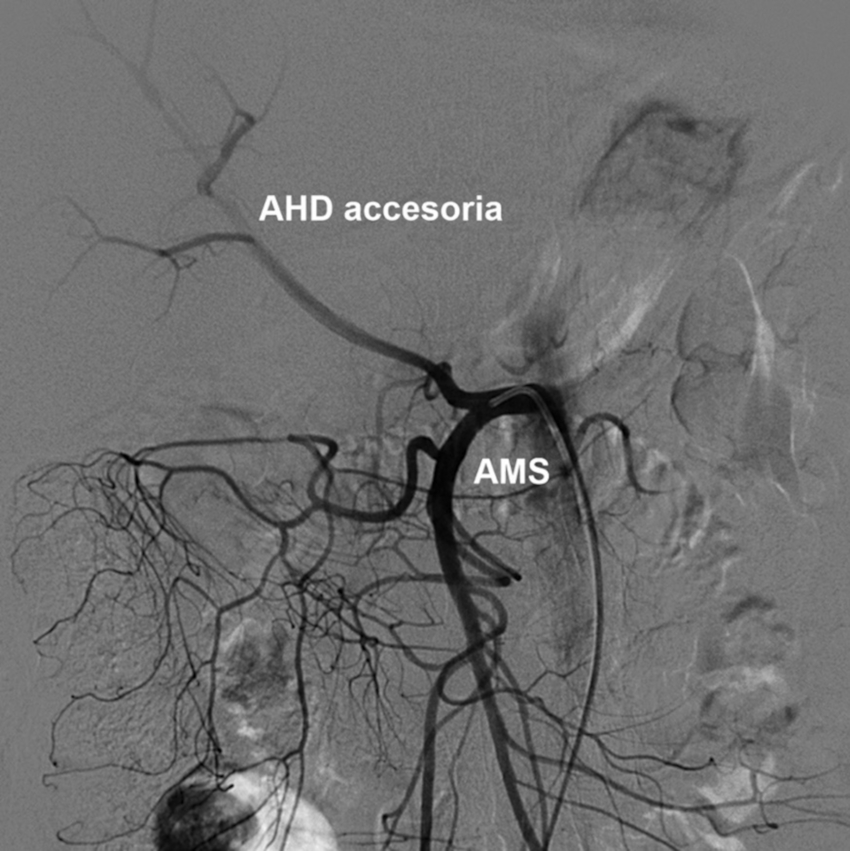

Tipo 6: AHD y AHI con origen en la AHC. AHD accesoria desde la AMS (Figs. 11 y 12).

Tipo 9: la AHC emerge de la AMS (Fig. 17).

Además, se observaron variantes fuera de la clasificación de Michels en 6 casos (2.2%): ausencia del tronco celíaco en 3 casos, tronco celíaco mesentérico en 2 casos (Fig. 18), y arterias hepáticas aberrantes derecha e izquierda originarias de AMS en 1 caso. Asimismo, en 3 casos de la variante tipo 1 de Michels se observaron los hallazgos asociados del arco de Bühler (Fig. 19).

Las siguientes variantes más frecuentes halladas fueron los tipos 2, 3 y 9. Las prevalencias de los tipos 2 y 3 fueron cercanas a la reportada por Fonseca-Neto et al. (18; asimismo, destacamos la prevalencia aumentada de la variante de Michels tipo 9 en nuestra serie comparada con otras publicaciones5,13,15,17,19. Al igual que Covey et al. (16, no hemos detectado la variante de Michels tipo 10; sin embargo, observamos otros hallazgos infrecuentes fuera de la clasificación de Michels, como dos casos de tronco celíaco-mesentérico (0.7%), ausencia del tronco celíaco (emergencia independiente de la AHC y esplénica), AHI accesoria emergente de la AGD y la emergencia de las AHD e AHI aberrantes de la AMS. También hallamos tres casos con arco de Bühler (1.1%), con una frecuencia similar a la de otros reportes (1.0 a 4.0%)20.